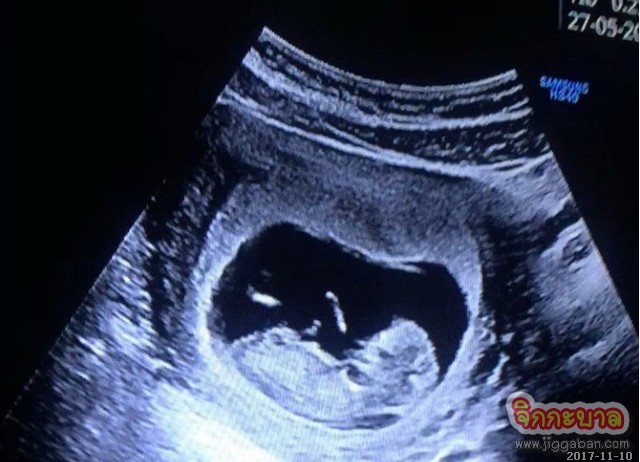

กรี๊ดเบอร์แรง ยินดีกับ ดีเจดร.อั๋น ภูวนาท คุนผลิน จากกรีนเวฟ 106.5 เอฟเอ็ม สามีสุดหล่อของ คุณจ๋า อลิสา พันธุศักดิ์ ภรรยาคนสวยที่กำลังจะมีสมาชิกใหม่ให้ครอบครัว สมใจสักทีเพราะทั้งคู่ตั้งหน้าตั้งตารอกันมาพักใหญ่ งานนี้คุณพ่ออั๋นเค้าคุยเอาไว้ในอินสตราแกรมว่า “นับว่าที่ทำๆ ไปไม่เสียแรงและทรัพยากรโลก” แหม! ไม่ค่อยเลยนะคุณพ่อ ก็ต้องขอแสดงความยินดีกับครอบครัวของทั้งคู่ด้วยนะคะ